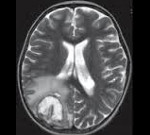

• Нейровизуализация. Применяют КТ или МРТ головного мозга, иногда - их комбинацию. Томограммы свидетельствуют о наличии абсцессов, ишемических участков с геморрагиями, внутримозговых кровоизлияний.